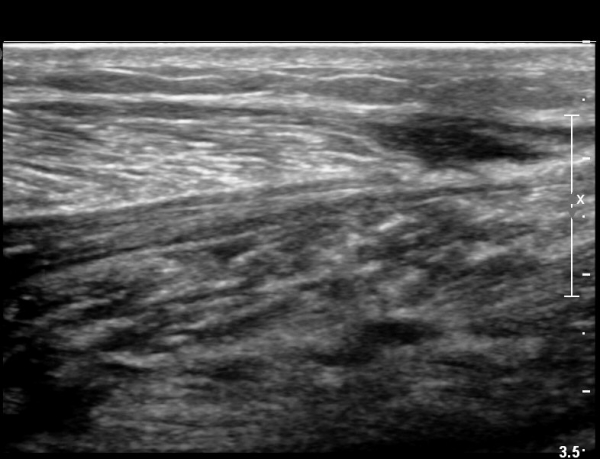

³»Ãø ºñº¹±Ù Á¾´Ü¸é°Ë»ç¿¡¼­ ³»Ãø ¹èº¹±Ù ¸»´ÜºÎ ÆÄ¿­°ú °¡Àڹ̱٠½ÉºÎ¿¡ ¼ö¾×Àú·ù°¡ °üÂûµÊ(»çÁø 1, 2).